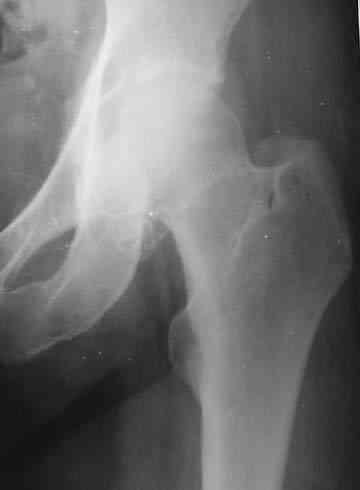

Пациентка И., 1952 года рождения. При первом поступлении пациентка предъявляла жалобы на резкую боль в левом тазобедренном суставе, возникающую при движении.

Боль постепенно усиливалась в течении последних 2 лет. Лечилась амбулаторно у невролога по месту жительства с диагнозом остеохондроз поясничного отдела позвоночника, корешковый синдром. В общих и биохимических анализах крови изменений не отмечалось, ревматоидный фактор (РФ), С-реактивный белок – в пределах нормы. Рентгенологическое исследование. В прямой и боковой проекции левого тазjбедренного сустава отмечается уплотнение крыши вертлужной впадины. В мягких тканях определяются округлой формы участки неравномерного обызвествления.Заключение. ДОА тазобедренного сустава. Хондроматоз слева в мягких тканях.Клиника. Видимых деформаций в области тазобедренного сустава нет. Ограничено отведение в левом тазобедренном суставе из-за болей до 20º. На основании клинических и лабораторных показателей был поставлен диагноз "Хондроматоз левого тазобедренного сустава". После стандартного предоперационного обследования выполнена диагностическая артроскопия тазобедренного сустава – обнаружены свободно лежащие внутрисуставные хондральные тела > 2 см в диаметре, хондромаляция хряща головки бедренной кости II степени. Выполнена боковая артротомия, внутрисуставные тела удалены, синовиальная оболочка частично резецирована. Послеоперационное течение – без осложнений. Швы сняты в срок, заживление первичным натяжением. Назначен курс лечебной физкультуры. Учитывая наличие рентгенологических признаков коксартроза, проведен курс внутрисуставной вискосуплиментарной терапии препаратами 1% гиалуроновой кислоты № 2.Осмотр через 1 месяц после оперативного лечения. Жалоб на боль при ходьбе нет, движения в полном объеме. Рекомендовано динамическое наблюдение раз в полгода и контрольная рентгенография через год